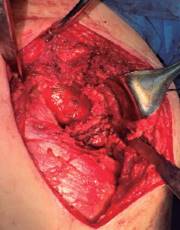

Se decidió llevar a cabo tratamiento quirúrgico que consistió en colocación de malla de titanio (Figura 3), la cual se fijó con dos tornillos de 1.5 × 1.0 cm para cubrir defecto acetabular, además de impactación de autoinjerto y aloinjerto cadavérico (ambos de cabeza femoral) (Figura 4) más colocación de artroplastía total de cadera derecha con componentes acetabular y femoral no cementados.

Figura 3: Malla de titanio para colocar y fijar con tornillos posterior a la impactación del injerto óseo.

La artroplastía total de cadera se realizó con una prótesis con sistema DePuy Synthes de Johnson & Johnson (Warsaw, IN, USA) con una copa acetabular no cementada Pinnacle Porocoat Acetabular Shell Multi-Hole II de 58 mm, la cual se fija con tres tornillos de 6.5 × 20,2 y 30 mm,1 inserto de polietileno de 32 mm, cabeza femoral metálica de 32 mm +1 y vástago femoral no cementado Summit 12/14 estándar #1 de 125 mm. El reemplazo articular se llevó a cabo por medio de un abordaje lateral directo donde, previo a la colocación del componente acetabular, se impacta autoinjerto y aloinjerto de cabeza femoral con el apoyo de la rima acetabular en sentido reverso para posteriormente colocar malla de titanio (Figura 5). La herida se cubre con un apósito convencional estéril y se toma control radiológico postquirúrgico con una proyección anteroposterior de pelvis (Figura 6).

Figura 5: Malla de titanio colocada en defecto acetabular posterior a la impactación del injerto óseo mediante un abordaje lateral directo.